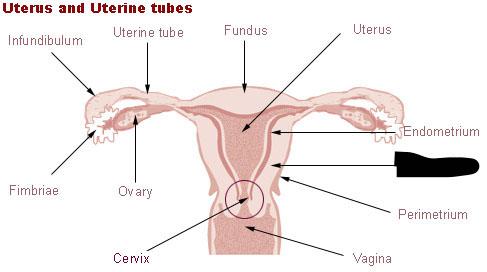

Broad ligament

Cervix

Corpus luteum

Endometrium

Fimbriae

Mature (=Graafian, = antral) follicle

Myometrium

Overian ligament

Ovary

Perimetrium

Primordial/primary/secondary follicle

Round ligament (of uterus)

Uterine (=fallopian) tube

Uterus

Vagina